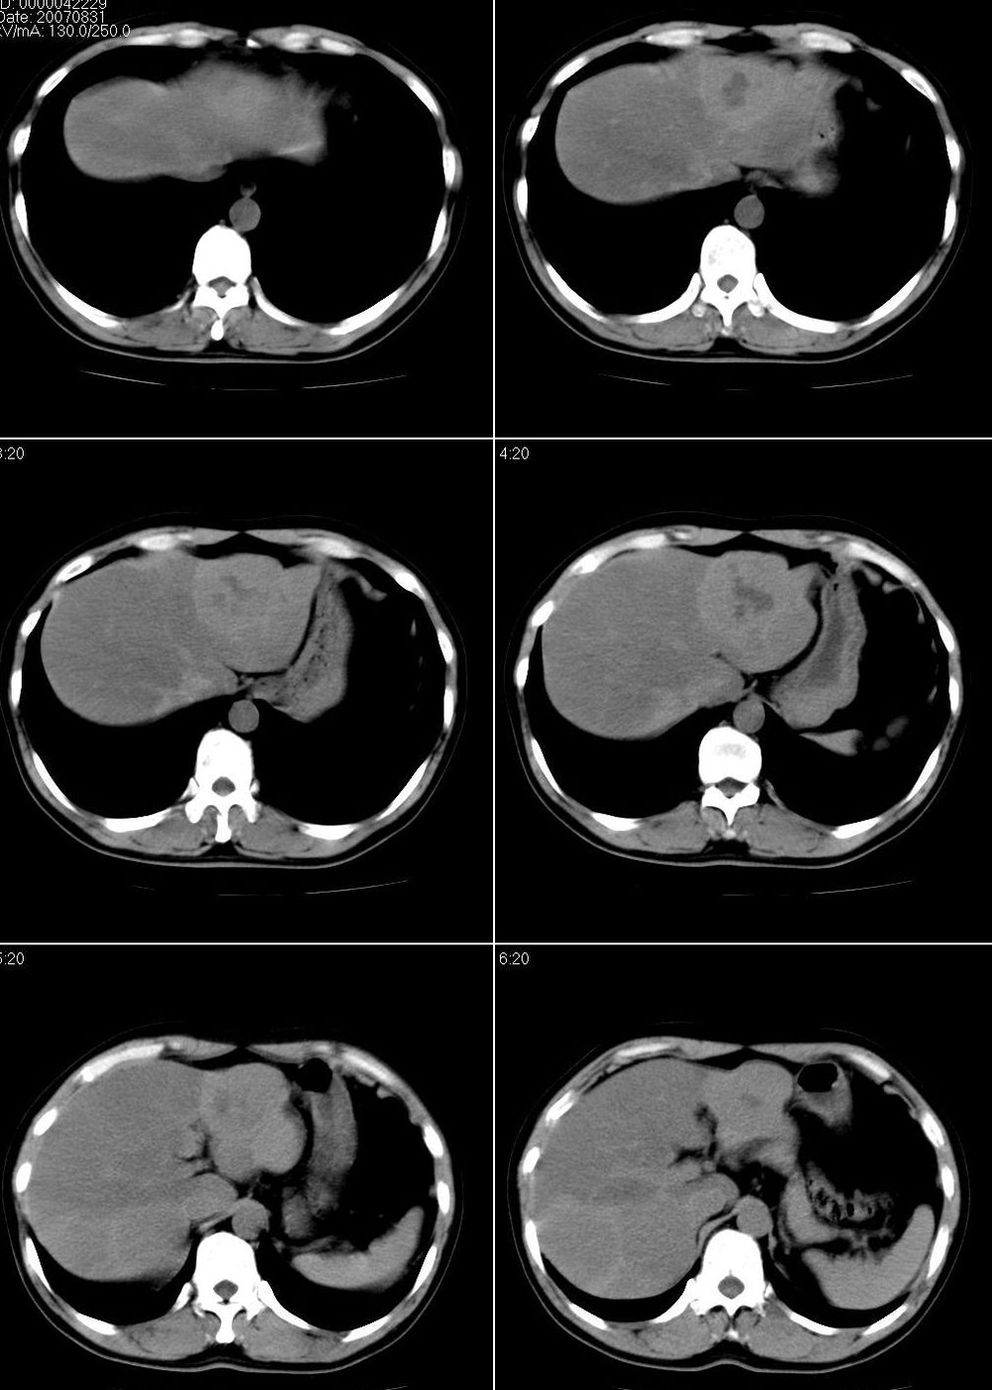

男,43岁。体检发现肝脏病变

肝局灶性脂肪肝 肝左叶外侧段占位病变,建议加强

考虑肝左叶癌并脂肪肝,肿块在脂肪肝衬托下呈高密度影,其内可见坏死灶,建议增强

肝右叶密度均匀减低,左叶增大,表面凹凸不平,内有低密度影。脾不大其密度较肝稍高。考虑1脂肪肝2肝左叶占位。建议增强。

1)局灶性脂肪肝2)肝左叶外侧段内占位,建议强化

肝局灶性脂肪肝 肝左叶外侧段1)肝海绵状血管瘤2)肝ca

肝右叶密度均匀减低,左叶增大,表面凹凸不平,内有低密度影。考虑1局灶性脂肪肝 2肝左叶占位。建议增强。

下缘与胃窦关系密切,会不会是来源于胃的间质瘤??